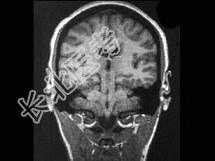

- 单项选择题男,32岁, 头痛、抽搐3年余,MRI检查如图, 最可能的诊断是 ( )

A、先天发育不全

B、灰质异位

C、正常颅脑

D、片状脑梗死

E、脑水肿